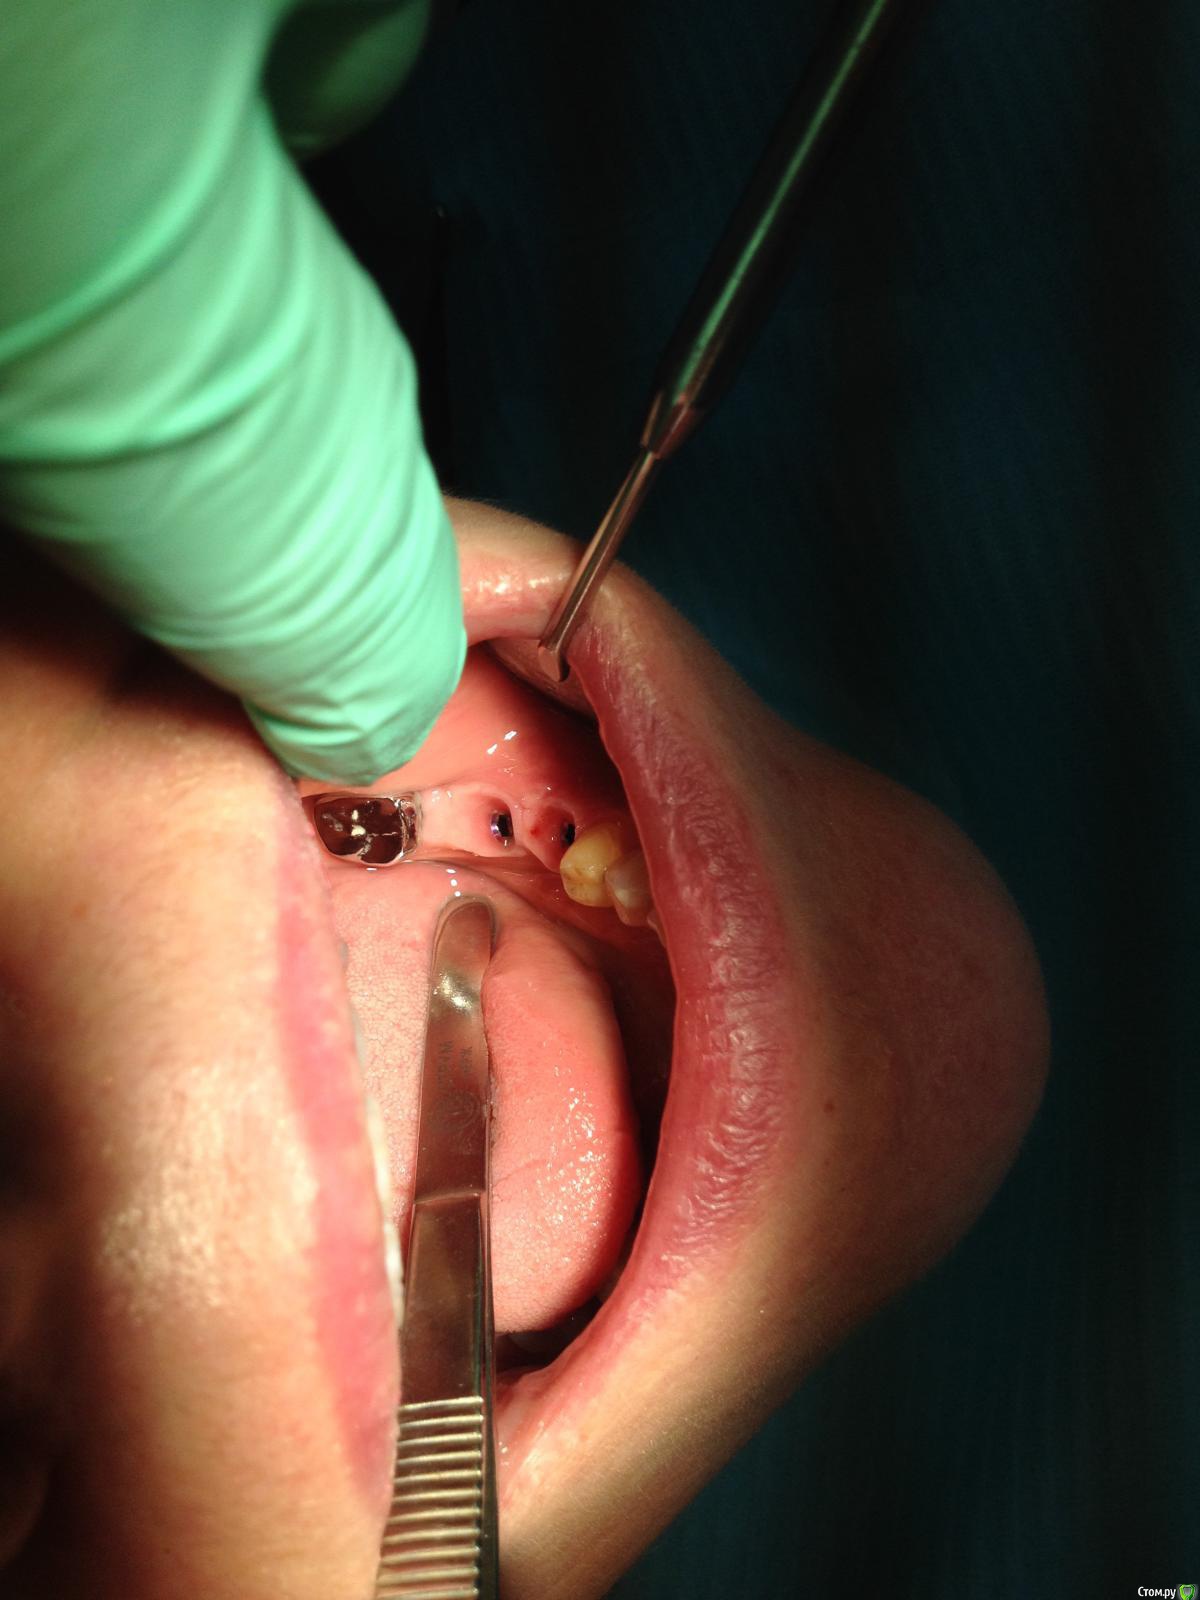

Ст@ся Опубликовано 1 августа, 2016 Поделиться Опубликовано 1 августа, 2016 В общем, опять все накрылось(Даже не знаю как быть дальше.Таких неприятностей с ССТ еще не было. Думаю, что не смогу исправить ситуацию.Под хлогрексидином ведите до полного заживления. Сделайте хорошие временные коронки и через 3 месяца оцените ситуацию. 1 Ссылка на комментарий

АнтонТЛТ Опубликовано 1 августа, 2016 Поделиться Опубликовано 1 августа, 2016 нить толстовата и не моноС 5/0 идет моно Ссылка на комментарий